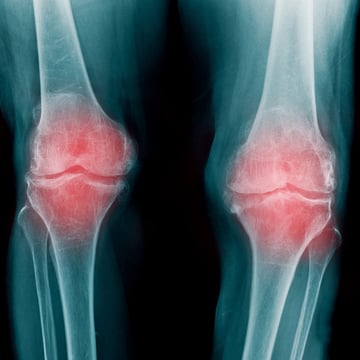

変形性膝関節症(膝OA)高齢膝について

変形性膝関節症とは、特に女性に多く見られる症状で年齢が上がるほど罹患率は高くなります。 近年の生活習慣の影響で40代から膝の内側に痛みを抱える方も増えてきています。 放置してしまうと骨に負担がかかり変形性膝関節症の症状が出現してしまいます。

症状としては階段や立ち上がる時の痛み、水が溜まる、O脚変形、膝が伸びきらないなどがあります。